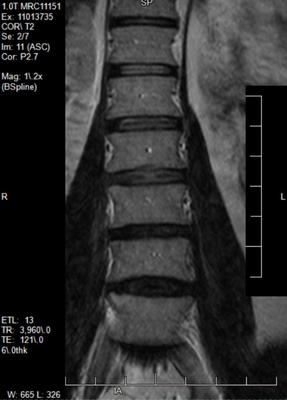

With neurosurgeon and go from there. 10 causes of pain down your leg. Pain in your lower back that is associated with shooting pains down the back of one or both legs indicates sciatica or discogenic pain. Sciatica is a shooting pain that begins in the lower back, radiates into the buttock and down the back of one leg.